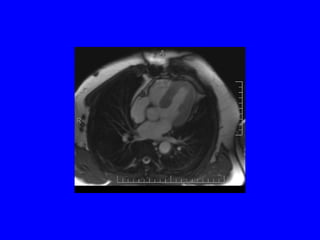

Dilated LV and RA

Ao valv, pap muscle, rt pleural fluid, dilated lv

Coronal MRI shows aorta, av, lv (can eval for stenosis and regurg) Spin echo “black blood” anatomy Gradient echo “white blood” function & flow